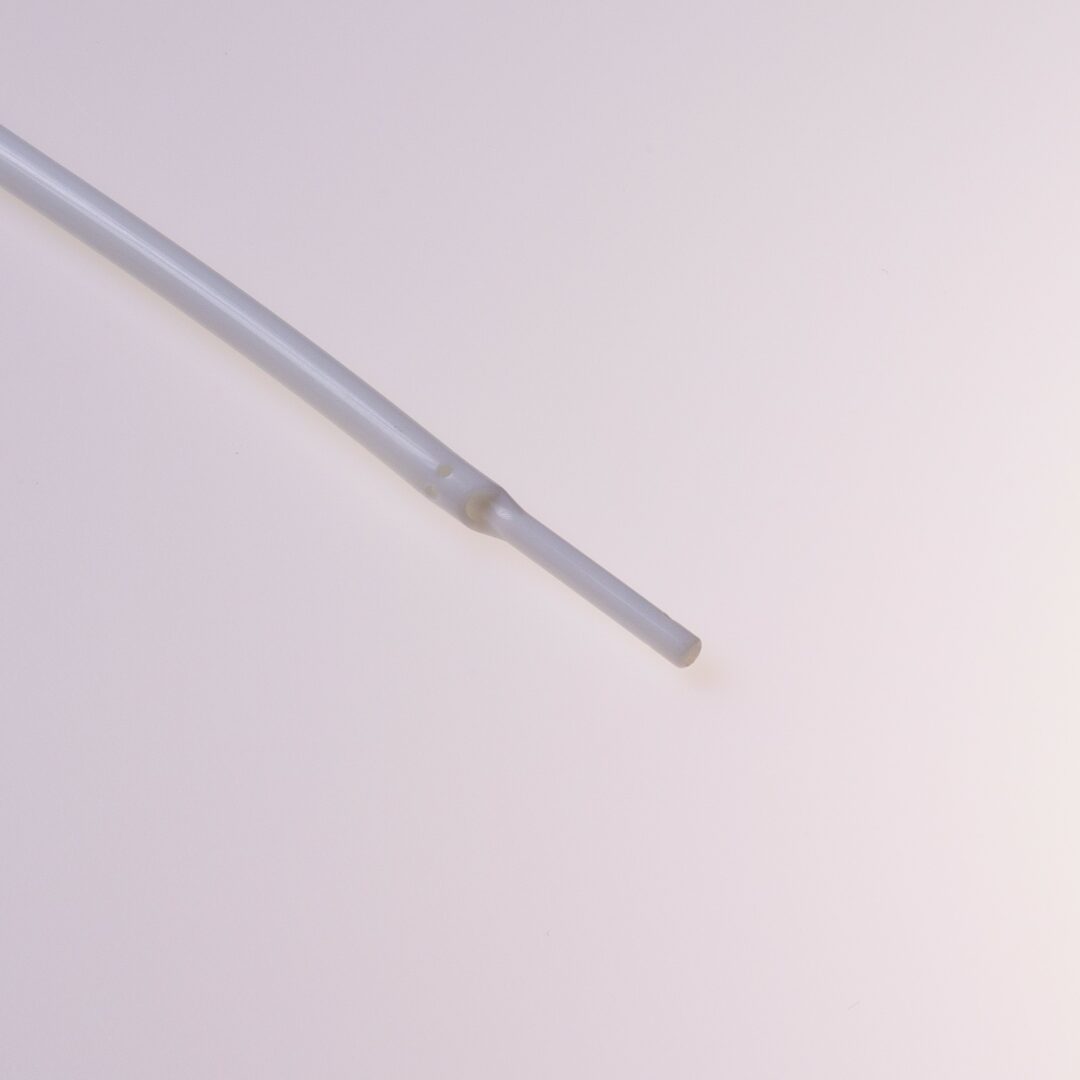

Tip Design

Der HFS Hemo Flow® verfügt über ein „Tap Tip“ Spitzendesign.